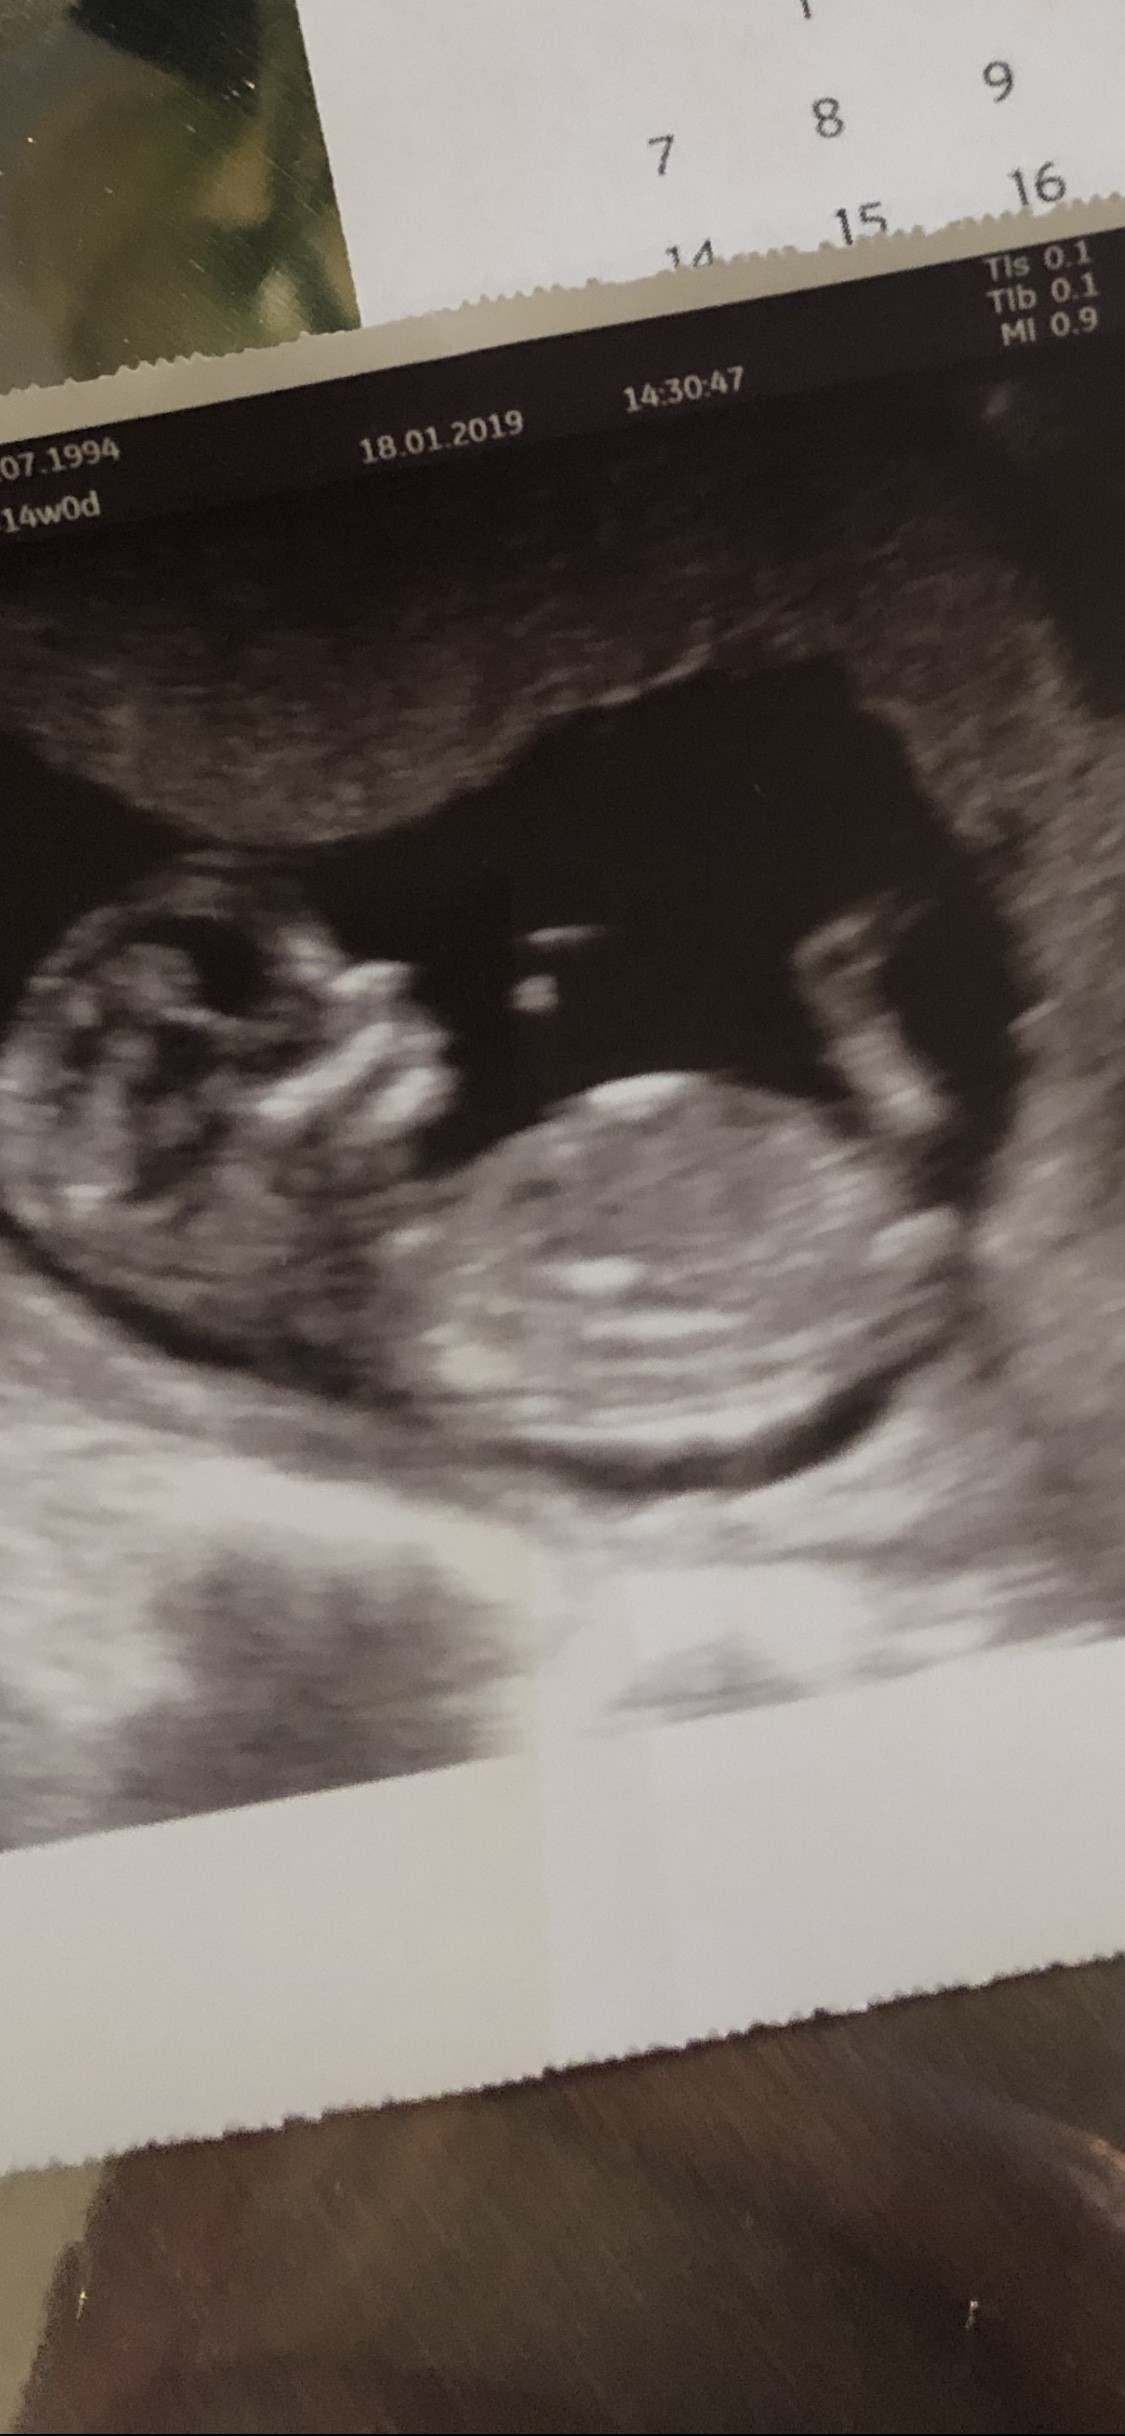

Ohh u nas tez wszyscy ‚napaleni’ na córeczkę. Teściowie maja 2ch synów i jednego wnuka a moi rodzice 2 córki i to będzie ich pierwsze wnuczatko. Na usg dzidzia troszkę się obróciła na boczek i ja nie widzę nic pomiędzy nóżkami ale położna mnie wyśmiała ze jeszcze za wcześnie gdybać Zobacz załącznik 938896